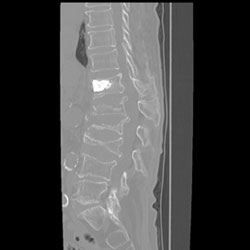

腰椎後方固定術

腰椎後方固定術とは、ケージやスクリューを用いて脊椎を固定する方法です。

手術は全身麻酔下で行われて、腰椎椎間板ヘルニア、腰椎脊柱管狭窄症、腰椎変性すべり症、腰椎すべり症、変性側弯症などにより椎間板の変形を起こす疾患が対象となります。

前方椎体固定術

椎体圧迫骨折や脊椎感染症などで前方から神経が圧迫されている場合や、脊柱変形や腰部脊柱管狭窄症・腰椎すべり症に対し、自分の骨や人工骨を入れた金属を設置し、固定します。後方の固定追加をすることもあります。

術前

椎体が前へずれています。

MRI

MRI

レントゲン

レントゲン

術後

椎体の骨のずれが矯正されています。

レントゲン

レントゲン